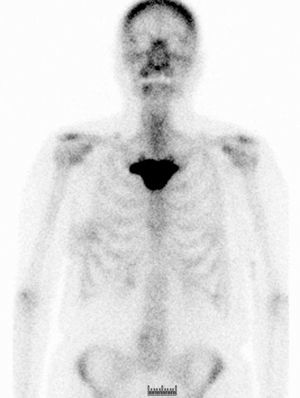

En el estudio de extensión de la enfermedad solicitado, se evidenció imagen gammagráfica de lesión blástica, difusa, en el manubrio esternal, sospechosa de enfermedad de Paget o de lesión metastásica (fig. 1). Se completó el estudio con radiografías de tórax, columna lumbosacra y pelvis (figs. 2 y 3), en las que solo se evidenció aumento de densidad interapofisaria de L4 y L5. Posteriormente, se solicitó TC torácico, según recomendaciones de Medicina Nuclear, que informó de esclerosis en el manubrio esternal, sugerente de metástasis (fig. 4).

Ante la dificultad del caso, se realizó sesión clínica en la que intervinieron los servicios de Oncología Radioterápica, Reumatología, Radiodiagnóstico y Medicina Nuclear para revisar el caso. Se concluyó con el diagnóstico definitivo de síndrome de SAPHO, ya que la paciente presentaba uno de los criterios de inclusión descritos por Benhamou5, la hiperostosis de la pared anterior del tórax con o sin afectación dérmica, y ningún criterio de exclusión (tabla 1). Se declinó en ese momento realizar biopsia de la lesión, pendiente de ver evolución radiográfica. Se decidió realizar un control gammagráfico y con TC osteoarticular11 a los 6 meses, sin evidenciar cambios reseñables, y se descartó definitivamente biopsia de la zona afectada al no haber imágenes que sugirieran agresividad de la lesión. La paciente durante el tratamiento no requirió ningún tipo de medicación analgésica. Por nuestra parte, no incluimos la zona afectada en el campo de tratamiento, para evitar modificaciones provocadas por la radioterapia que pudieran dar lugar a confusión a la hora de valorar la evolución de la lesión. Después de 18 meses de seguimiento, la paciente permanece en respuesta completa tumoral y, por tanto, libre de enfermedad.